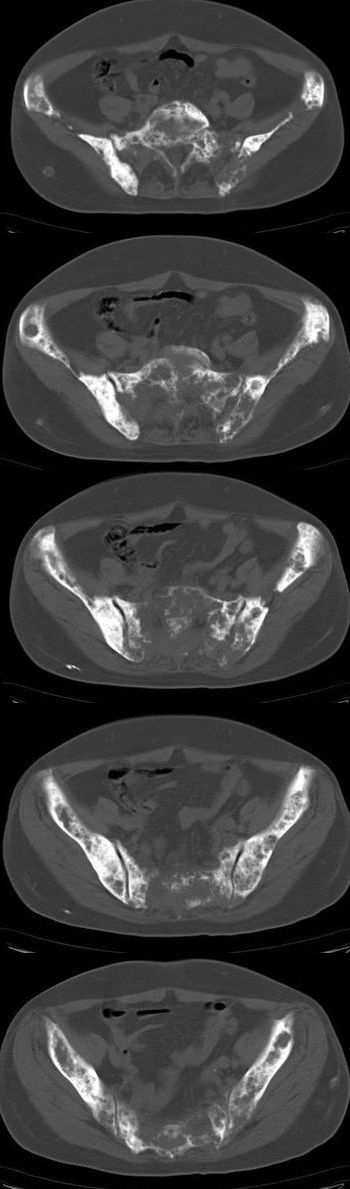

标题: CT13121:女,54岁。乳腺癌术后8年。 [打印本页]

女,54岁。乳腺癌术后8年。现感觉左腿酸困不适,并向下放散。左腿僵硬,不由自主。

典型溶骨型转移瘤。

骨盆及腰椎多发性溶骨性转移瘤.

成骨及融骨转移。

结合病史考虑乳腺癌术后多骨骨转移。

患者臀部皮下脂肪、筋膜、臀大肌处多个小结节、钙化影,看来挨了不少肌肉注射的苦头

支持 骨转移瘤---混合型以溶骨为主

结合临床考虑多骨多灶性溶、成骨性转移。